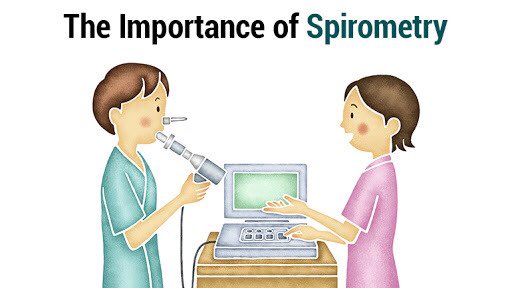

🔴 رابعا : كيف نسوي له التشخيص

dignosis؟

*a physical exam

•Examine your nose, throat and upper airways.

•Use a stethoscope to listen to your breathing.

*your symptoms

*lung tests ( #Spirometry )

الزبدة

اول مايجينا بالاعراض

يتم تحديد تشخيصه عبر #سبيرومتري

بفسره لكم 👇🏻

يلا لنبدأ بالشرح بهذا الثريد 😍👇

#سبيرومتري :

هذا الجهاز يطلع لنا حجم الهواء الخارج

(اول شي نقوله خذ نفس عميق واستنشق "طلع الهواء"في هذا الجهاز اقوى ماعندك )

ويطلع لنا 3 اشياء :

1-force vital cabasty (FVC)

يعني السعة الحيوية المدفوعة بقوة

الانسان الطبيعي 5L

#يتبع 👇🏻

#سبيرومتري :

هذا الجهاز يطلع لنا حجم الهواء الخارج

(اول شي نقوله خذ نفس عميق واستنشق "طلع الهواء"في هذا الجهاز اقوى ماعندك )

ويطلع لنا 3 اشياء :

1-force vital cabasty (FVC)

يعني السعة الحيوية المدفوعة بقوة

الانسان الطبيعي 5L

#يتبع 👇🏻

2-force expiratory volume FEV1

يعني الحجم المزفور بالثانية الواحدة

الانسان الطبيعي

3-FEV1/FVC

حاصل القسمة بينهم ويطلع نسبة

الطبيعي فوق 80%

يعني يستطيع الانسان ان يخرج بالثانية 80% من السعة الاجمالية في داخل الرئة

صاحب الربو اقل من 60% 😔

ونقدر بعدها نشوف استجابة المريض لموسعات الشعب

اذا بعد ما اعطيناه موسع شعب وزاد بنسبة 15% هذا دليل ان عندة ربو

وهذا الاختبار من اهم الاختبارات لتحديد الخطة العلاجية والتشخيص يلا نبدأ تصنيفات انواع الربو

اذا بعد ما اعطيناه موسع شعب وزاد بنسبة 15% هذا دليل ان عندة ربو

وهذا الاختبار من اهم الاختبارات لتحديد الخطة العلاجية والتشخيص يلا نبدأ تصنيفات انواع الربو